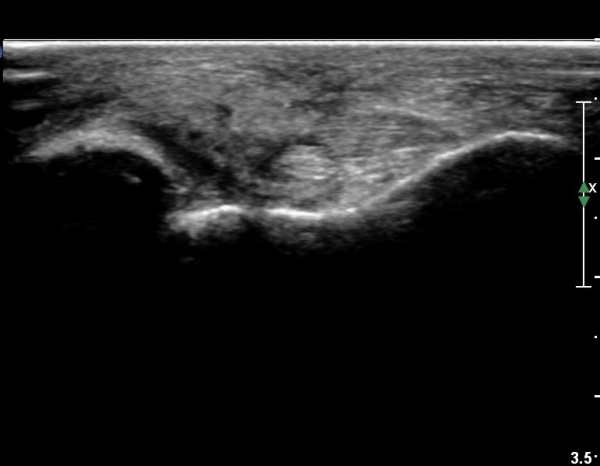

Àü°ÅºñÀÎ´ë ºÎÇϰ˻翡¼­ ÀδëÆÄ¿­ ºÎÀ§°¡ ¹ú¾îÁö°í °Å°ñÀÌ ¾ÕÀ¸·Î ´Ü°ÜÁö´Â ¼Ò°ßÀ» º¸ÀÓ(»çÁø 3, 4, ÷ºÎ µ¿¿µ»ó).